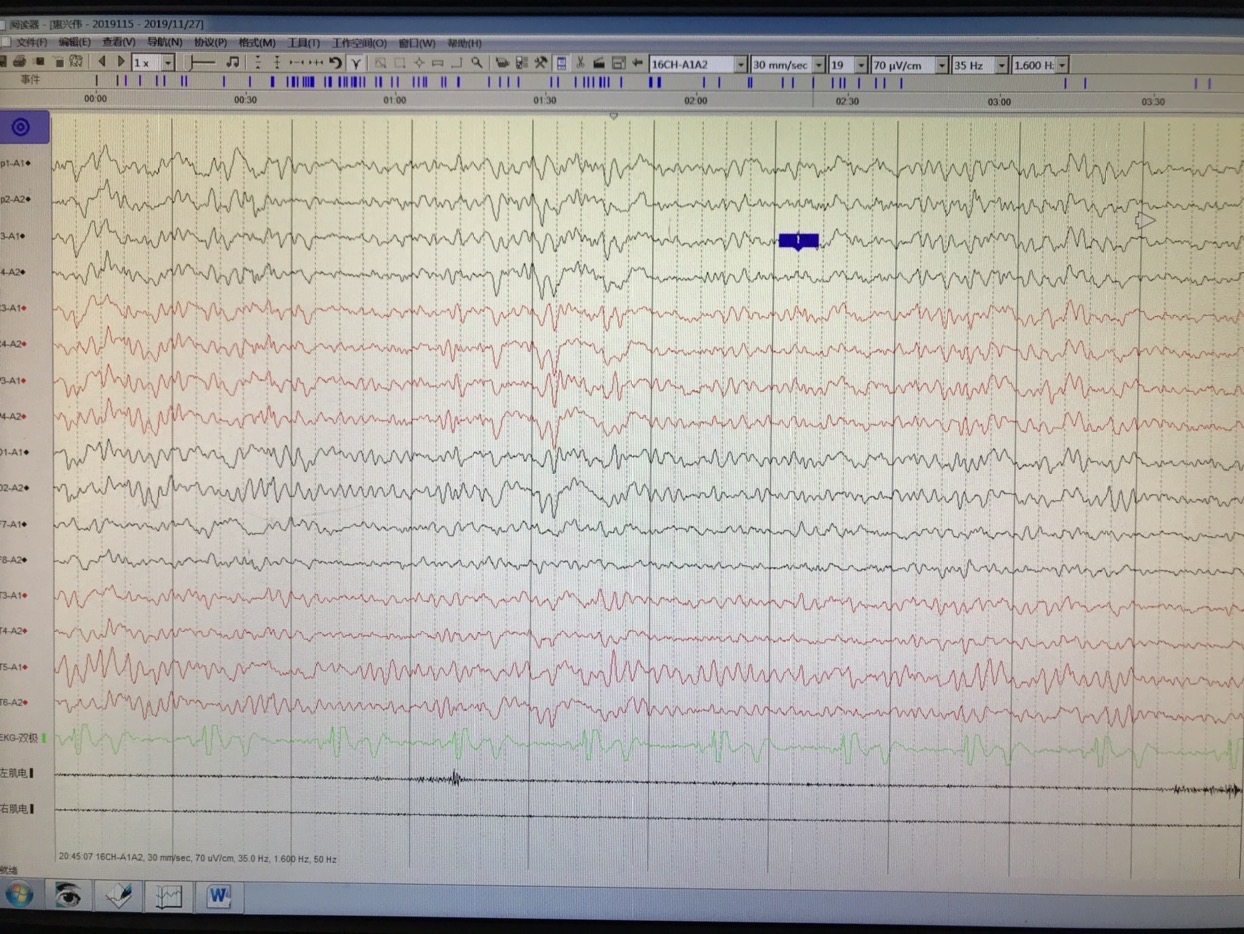

长程视频脑电监测提示左侧中央区、顶区、后颞区见中等量低-中-高波幅痫样放电。